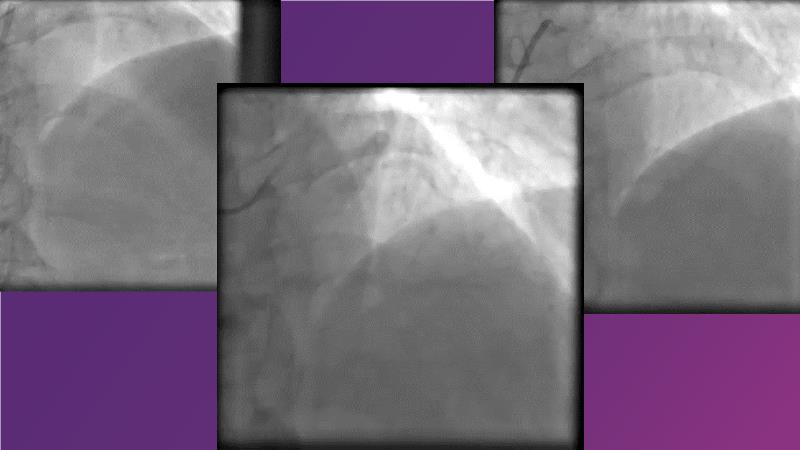

Complex coronary artery disease: can stents and DCB be complementary?

DES and DCB, can these two technologies be complementary for the treatment of the same patient? What are the advantages and how to proceed? You will know everything by watching this presentation based on concrete cases.

- To appreciate short and long-term angiographic results